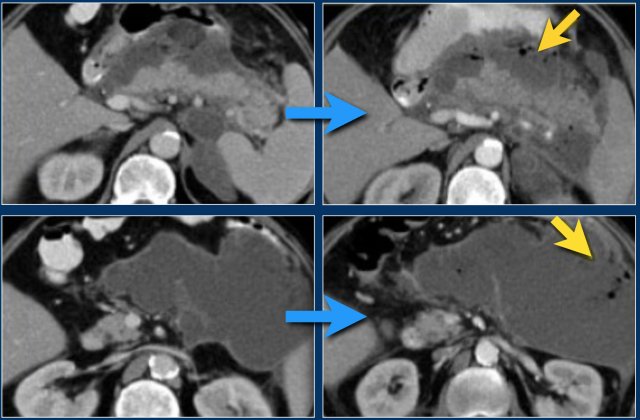

The findings are:

- Normal enhancement of the entire pancreas.

- Extensive peripancreatic collections, which have liquid and non-liquid densities on CT.

- There are at least two collections, but no pancreatic parenchymal necrosis (CTSI: 4).

- On day 18 there is expansion of the peripancreatic collections and an incomplete wall is present.

On day 5 this collection can be diagnosed as probable acute necrotic collection.

On day 18 an incomplete wall is present, but we can assume that in a couple of days this will be a walled-of-necrosis with a complete wall.

When peripancreatic collections persist or increase, it is usually due to the presence of fat necrosis.

Because fat does not enhance on CT, the diagnosis of fat necrosis can be difficult.